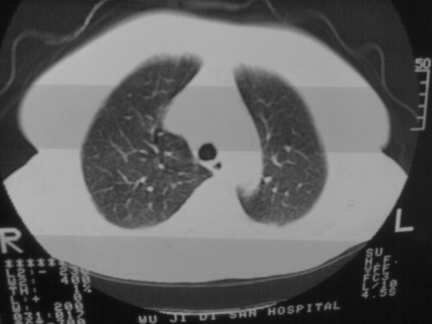

标题: CT13142:女 80 胸闷、气短、1w [打印本页]

标题: CT13142:女 80 胸闷、气短、1w

右肺炎性变,双侧甲状腺肿,胸膜肥厚。

右肺炎性变

右肺感染;双侧胸腔少量积液,心影增大,可能与心功不全有关;胸内甲状腺肿。

右肺炎性变,双侧甲状腺肿,胸膜肥厚,心影增大考虑心功能不全.

胸内甲状腺肿;右肺感染;双侧胸腔少量积液。

胸内甲状腺肿;右肺中叶感染;双侧胸腔少量积液;心影增大,考虑有心功能不全。